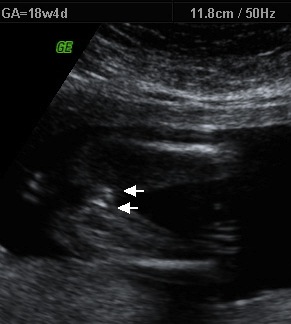

Taken at somewhere between 18 weeks and 19 weeks.

Defo girl no scrotum seen ! The part you see in the middle is just swollen clitoris which is normal x